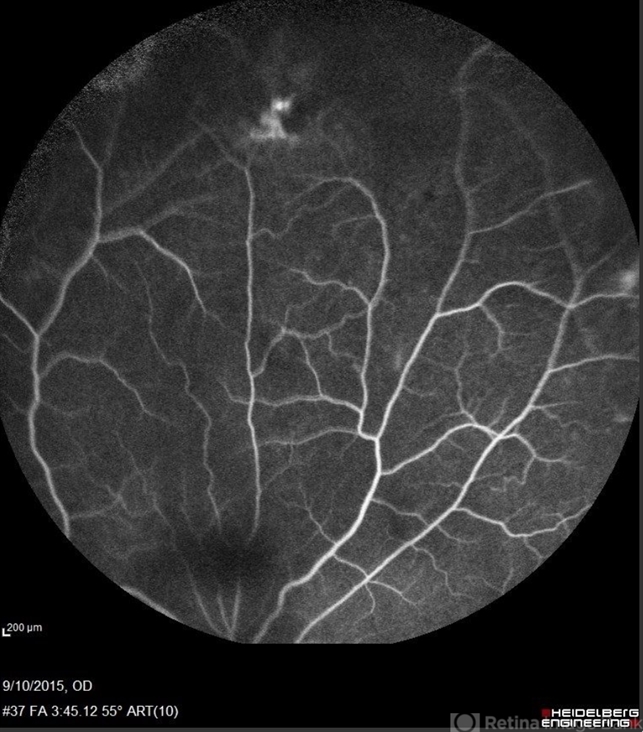

- Sickle Cell Retinopathy

- sickle cell retinopathy, peripheral retinal neovascularization, sea fan

- Angiography showed normal vessels posteriorly but severe capillary drop out throughout the periphery OU with scattered severe neovascularization at the edge of the capillary drop out peripherally.